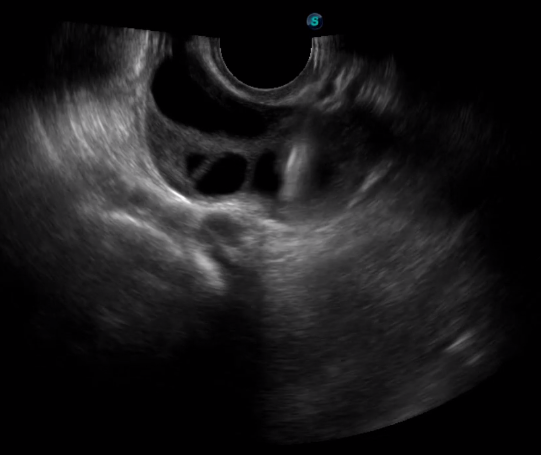

5   TEE

TEE(經(jīng)食道超聲心動圖)將超聲探頭置入食道內(nèi),從心臟的后方向前近距離探查其結(jié)構(gòu) ,克服了經(jīng)胸超聲檢查的局限性,避免肺內(nèi)氣體、胸壁脂肪、胸廓畸形等因素影響,觀察角度更多,圖像更加清晰,測量數(shù)據(jù)更準(zhǔn)確。

經(jīng)食道超聲 大動脈短軸